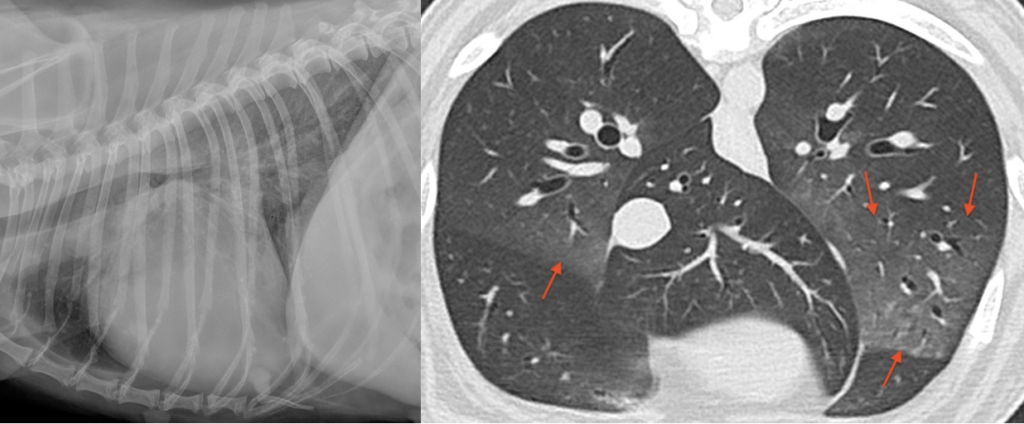

Figure 5 et 6 : opacification interstitielle caudodorsale en radiographie à gauche et plage interstitielle ventrale en tomodensitométrie à droite.